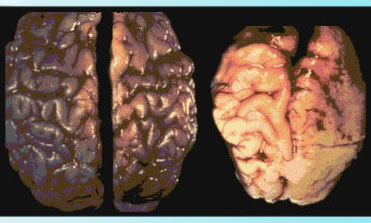

Brains of babies in utero are especially graphic… at left, a normal brain; at right, the brain of a fetus with fetal alcohol syndrome (caused by alcohol in the mother’s system).